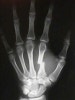

X-ray : Boxer's fracture(복서골절)

cf) Boxer's fracture(복서골절) : 5th metacarpal neck fracture

젊은 남성에게 다발하며 주먹으로 펀치기계나 벽을 치거나, 넘어지면서 땅을 쳐서 발생합니다.

다른 손가락을 살펴보아도 원래부터 약간 굴곡된 형태를 가지고 있어 처음 접하는 사람은 이것이 굴곡된 것인지, 부러진 것인지 모를 수 있습니다. 간혹 이번이 아닌 예전에 부러진 것이 굴곡된 채 저절로 유합된 사례로 인해 혼동을 겪을 수 있습니다.

보통 유합은 잘되나 부정유합이 많기 때문에 제대로 정복해 유합되는 것이 치료의 목표입니다.

대부분의 경우에 정복이 필요하며 정복을 해도 저절로 정복 소실이 오기 때문에 간단한 수술이 필요하기도 합니다.

금만 살짝 가서 정복이 필요없는 경우는 splint로 3주간 보호합니다.